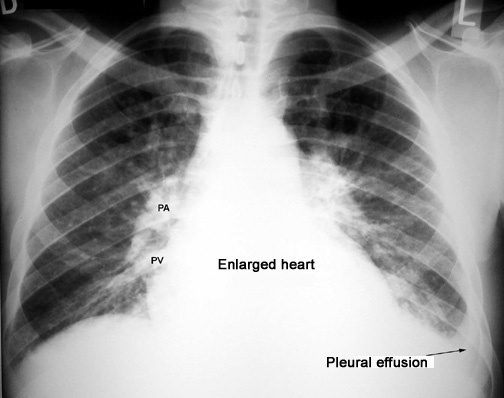

Loculated Pleural Effusion Definition / Learning Radiology - Hydropneumothorax - Pericardial effusion is defined as an increased amount of pericardial fluid.